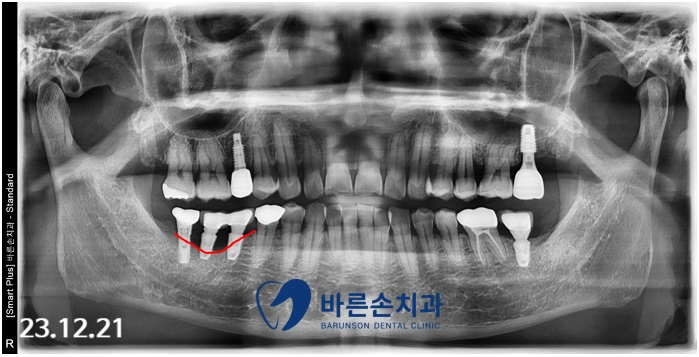

임플란트 재 수술

약 3개월 후,

이식된 뼈가 단단하게 자리 잡을 것을 확인 후

임플란트 재수술을 진행하였습니다.

식립된 임플란트가 뼈에 단단히 고정된 것을

확인 후 상부 임플란트 보철을 제작 하고

편하게 사용 중이십니다.

치료 후

치료 전후 파노라마 사진을 보면

임플란트 주변 치조골(뼈)의

형태가 달라진 것을 알수있습니다.